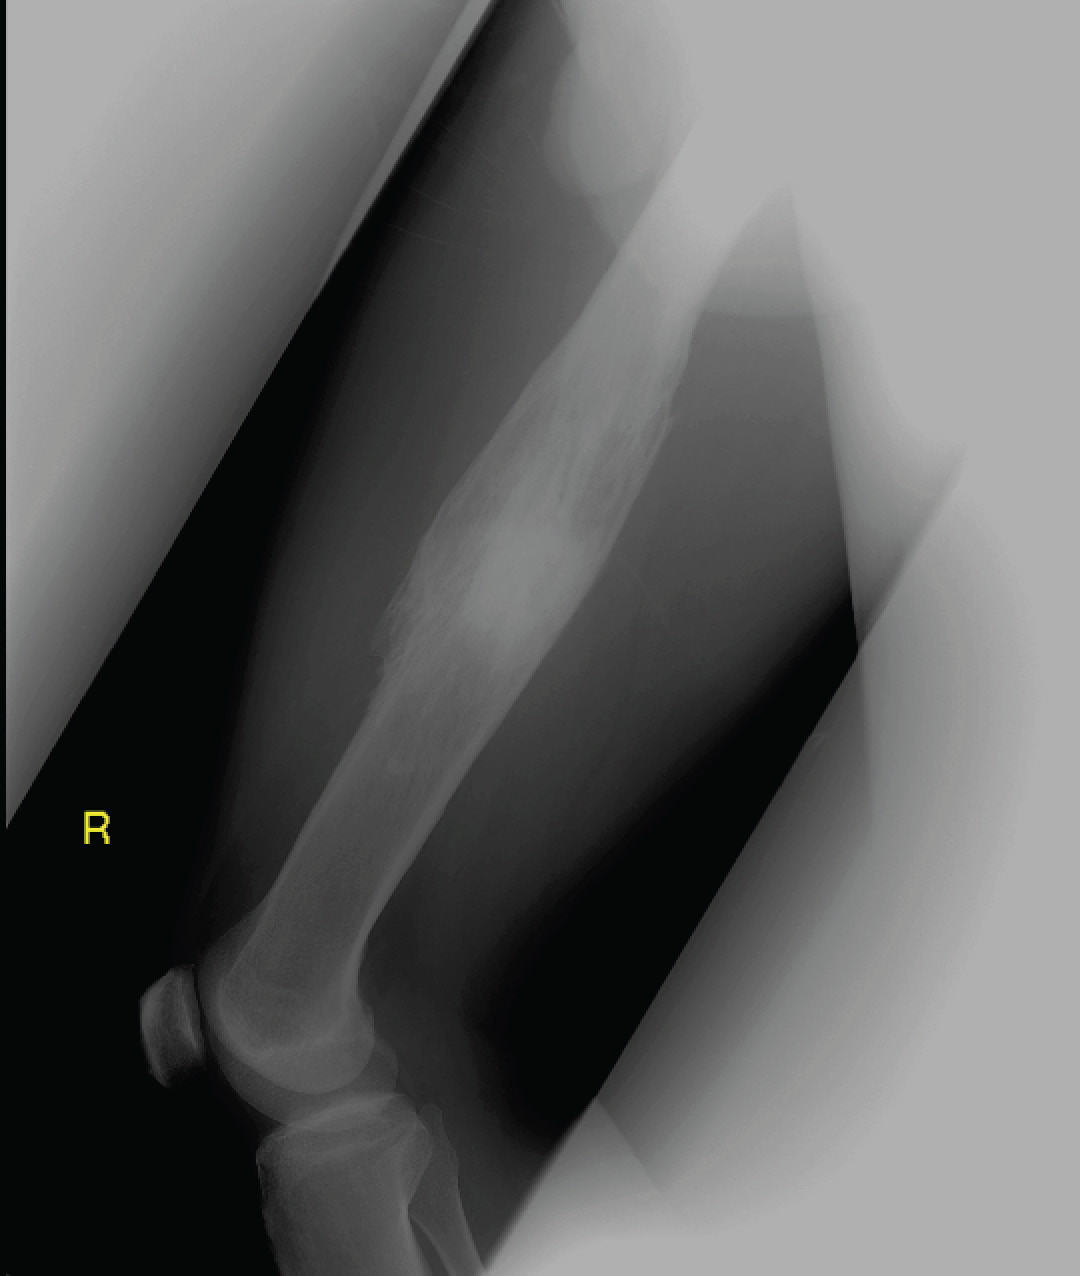

Clinical examination revealed mild erythema over the anterior surface of his right thigh. The X-ray is shown below.

This gentleman has chronic osteomyelitis of the femur resulting in mal-union and a central sequestrum (dead infected bone) with surrounding involucrum (new bone growth as a result of infection). These features are better appreciated on magnetic resonance imaging (MRI) – and a sample image is shown below.